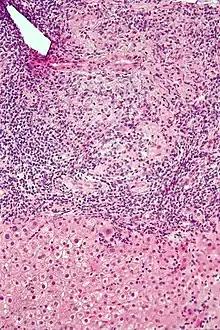

| Micrograph of PBC showing bile duct inflammation and injury, H&E stain | |

On microscopic examination of liver biopsy specimens, PBC is characterized by chronic, nonsuppurative inflammation, which surrounds and destroys interlobular and septal bile ducts. These histopathologic findings in primary biliary cholangitis include:[32]

- Inflammation of the bile ducts, characterized by intraepithelial lymphocytes

- Periductal epithelioid granulomas.

- Proliferation of bile ductules

- Fibrosis (scarring)